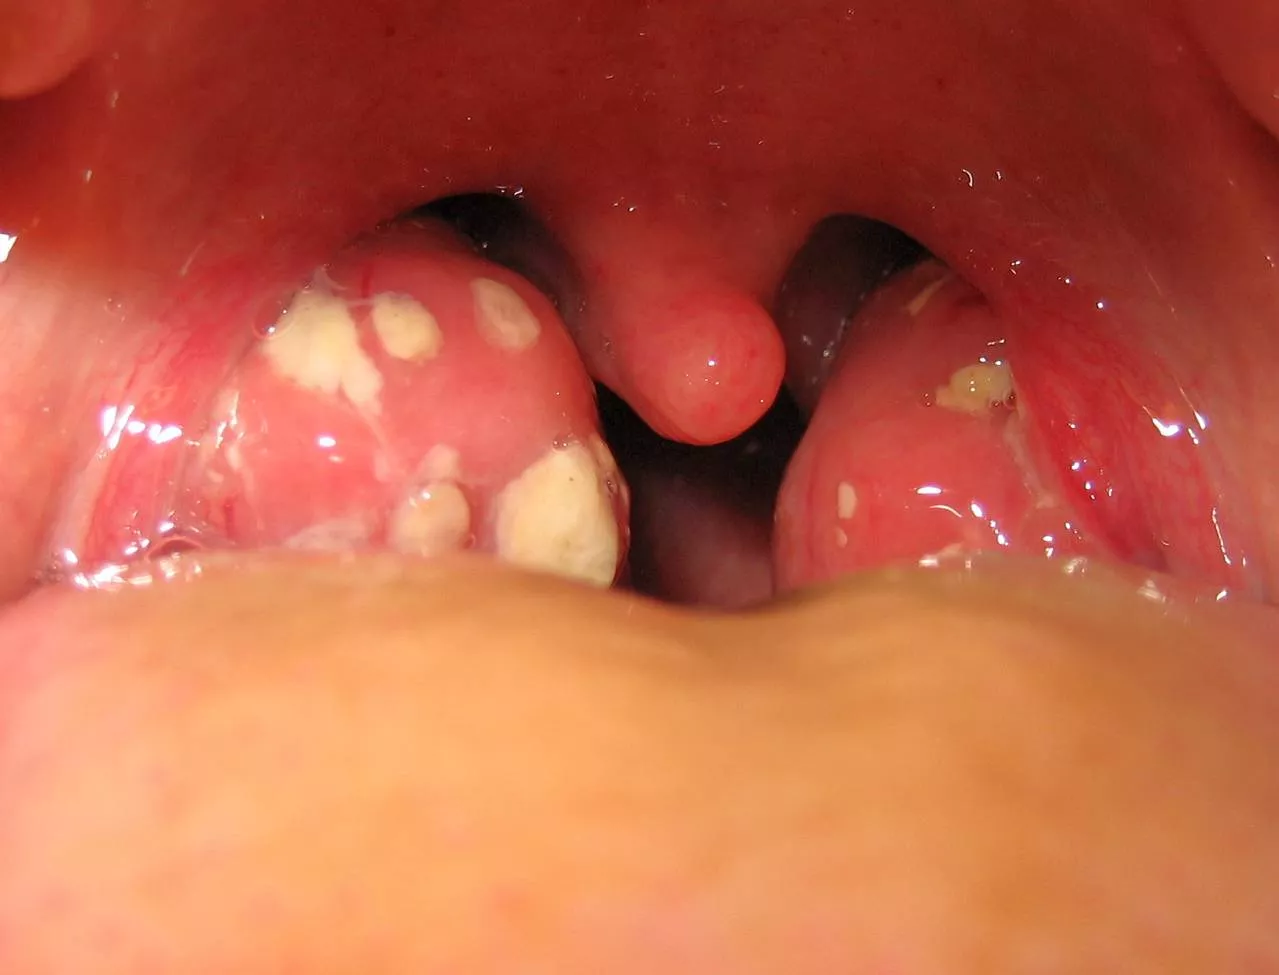

Hasonló okból a torokmandula is megnagyobbodhat, kívülről megtekintve akár össze is érhetnek, enyhébb – átmeneti – nyelési nehézséget okozhatnak. Utóbbi önmagában nem indokolja eltávolításukat, és az idő előrehaladtával a kisgyerekek többsége kinövi. Adott esetben mégis műtétre lehet szükség, cikkünk folytatásában ezt vesszük górcső alá.

- évente többször (>5) kiújuló tüszős (streptococcushoz köthető) mandulagyulladások, terápiarezisztens (idült) mandulagyulladás

আমার মুখে টনসিল এ ছোট ছোট সাদা দাগ দেখা যাচ্ছে এখন আমি কিছু খেতে গেলে অনেক ব্যাথা লাগে এবং টনসিল ও অনেক বড় হয়ে আছে এখন করনীয় কি?

Forduljon orvoshoz. Akár tüszős mandulagyulladása is lehet, amit antibiotikummal kell kezelni.